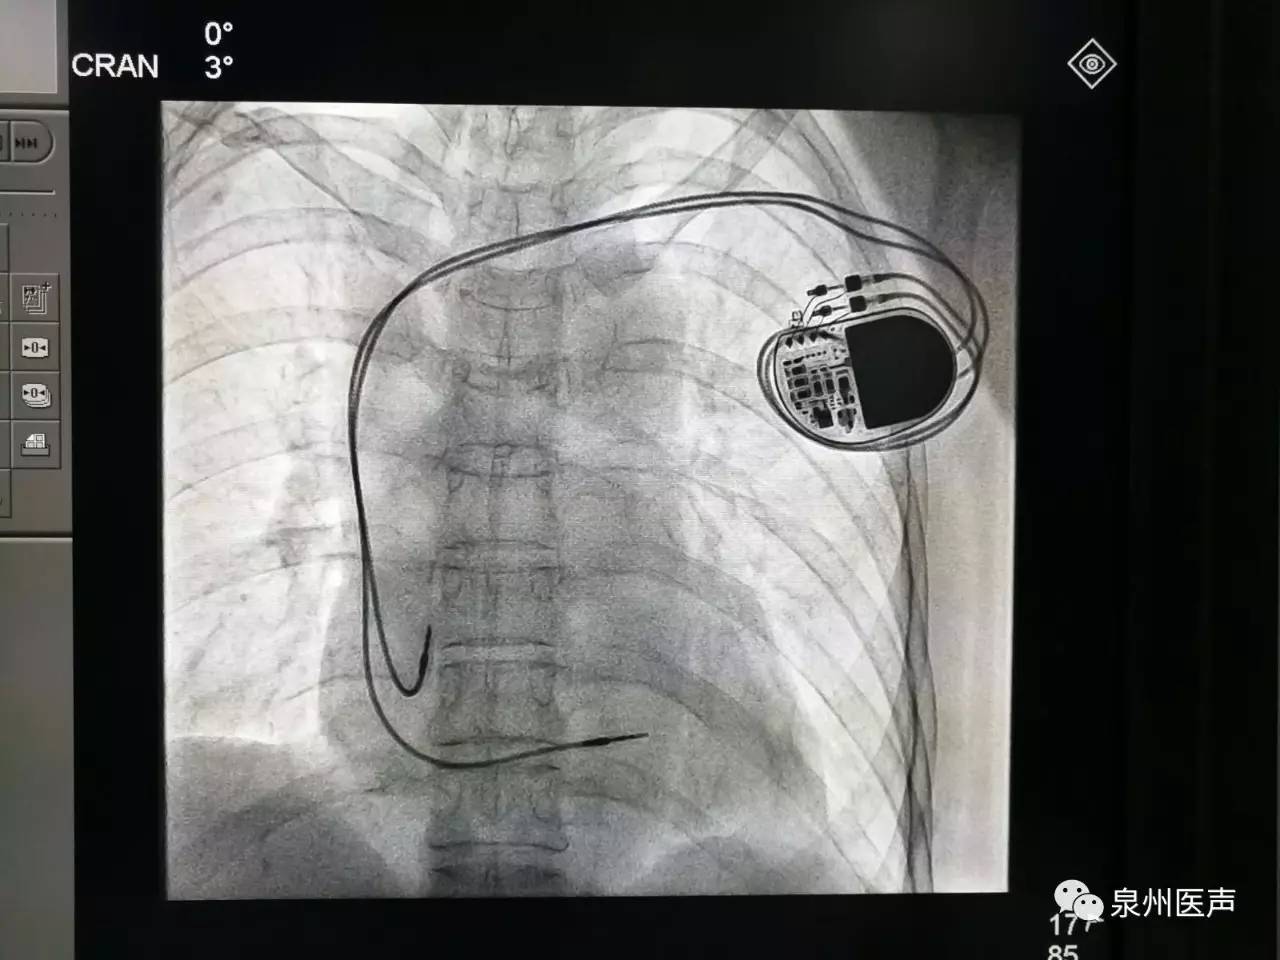

心臟起搏器的日常護(hù)理

心臟起搏器出院的宣教,是心內(nèi)科醫(yī)護(hù)人員不容忽視的一項工作